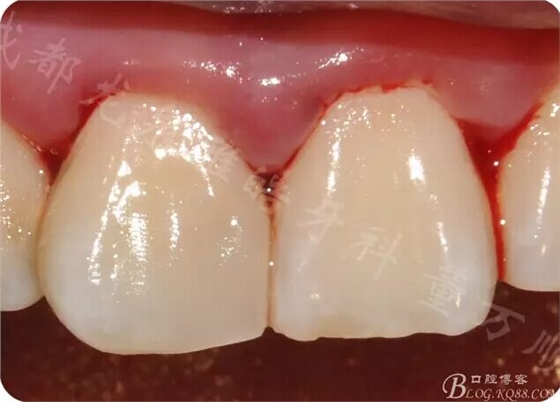

上橡皮章 果斷局麻下去除腐質(zhì)

開(kāi)始全是軟垢,涂布齲顯后 進(jìn)一步去除腐質(zhì)

果然近中髓角有穿髓孔 只能行根管治療

常規(guī)根管治療